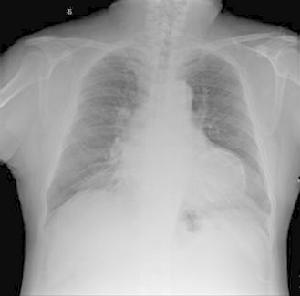

無症狀型心肌缺血透視①心電圖運動試驗陽性,而無症狀;

②冠狀動脈造影顯示有明顯的血管狹窄,而無症狀;

③未被識別或無症狀的心肌梗死;

④既往無症狀,但有陳舊性心肌梗死;

⑤慢性穩定性心絞痛,心肌缺血發作有時無症狀。臨床上三種類型的無痛性心肌缺血:Ⅰ型(完全無症狀SMI):一組對非因冠心病死亡者調查,生前無症狀,屍檢有冠心病男性6.4%,女性2.6%,這並不能肯定生前就一定有SMI。還調查了瓣膜病或心電圖異常者等無胸痛而做冠脈造影者,檢出無症狀冠心病4%。ErikssenThaulow入選2014名外貌健康的男性,40~59歲公務員,經ECG運動試驗,篩選出陽性86例,做冠脈造影69例證實有冠心病,其中50例完全無症狀占總數的2.5%。Ⅱ(心肌梗死後SMI):心肌梗死後,患者無症狀,做輕量級ECG運動試驗,有30%~42%可以檢出ST段降低,而沒有症狀,約占1/3。Ⅲ(心絞痛伴有SMI):多數慢性冠心病患者,經AECG監測有60%~67%可檢出ST段下移。在不穩定性心絞痛患者中檢出率更高。無痛性心肌缺血在冠心病者中相當常見。在心肌缺血發作時,無症狀的患者占了相當大的比例。